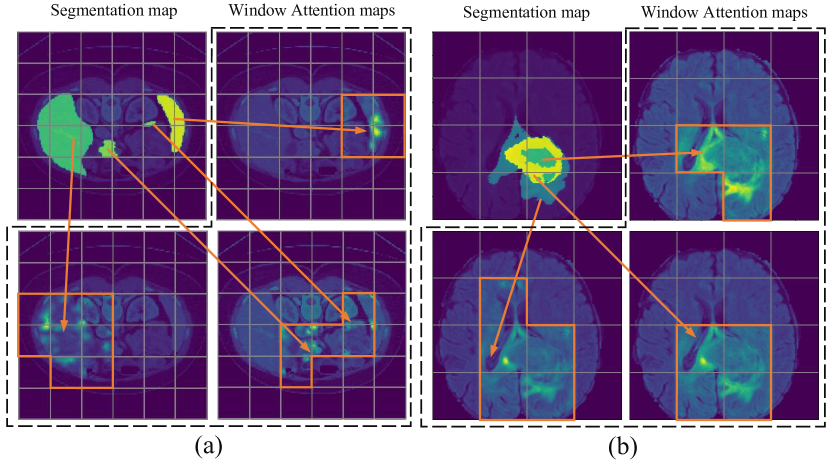

Refer to caption

Figure 5: Visualization of Window Attention weights on (a) Synapse and (b) MSD Brain datasets.

In this part, we provide visualization of Window Attention weights and the upsampled feature maps of different models in the upsampling path. To obtain our Window Attention weights, we retrieve the attention weights in WAD. Since each attention is computed inside local windows, we select the activated regions (the positive region in ground truth) and show the average attention weights of these windows with positive pixels. Feature maps after every upsample module are also visualized to demonstrate the effectiveness of our method. Figure 5 is the visualization of our Window Attention weights and shows how the attention is focused on the relevant pixels of the target area in each window. This further demonstrates the validation of our methods that by imposing an attention, model is prone to focus more on target. This enriches the information needed for segmentation task and leads to better performance. Figure 1 presents the upsampled feature maps after every upsample procedure on MSD Brain and Synapse datasets. It can be seen that our upsample method, taking advantage of self-attention, focuses better on target area than pure CNN-based method (i.e. ResUNet). Also, compared with ResUNet, our method shows a clear lesion that could further assist the diagnosis.